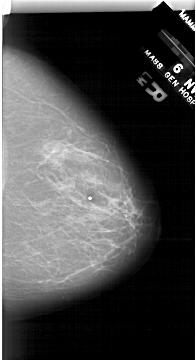

A_1687_1.RIGHT_MLO

LEFT_MLO LINES 6451 PIXELS_PER_LINE 3796 BITS_PER_PIXEL 12 RESOLUTION 43.5 OVERLAY